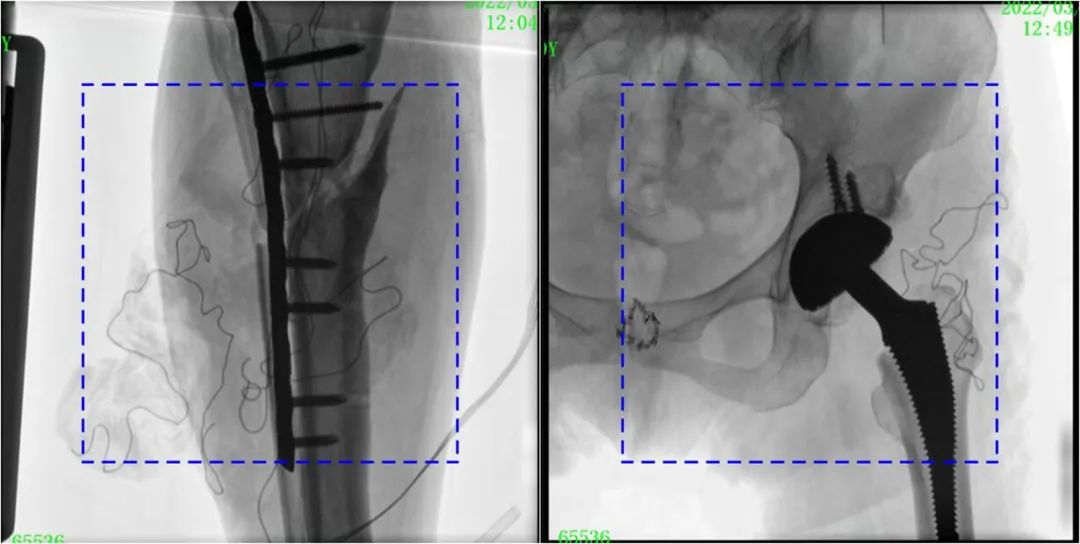

PLX119C臨床圖像與傳統圖像對比

注:藍色虛線內為傳統21CM×21CM平板的成像區域。

在進行髓內釘內固定術時,醫生需要同時觀察到入釘點和骨折部位的情況,普愛醫療大平板一體式C形臂采用30CM×30CM的平板探測器,能夠呈現更廣闊的成像面積,滿足大部分長骨髓內釘內固定術的攝片需求。